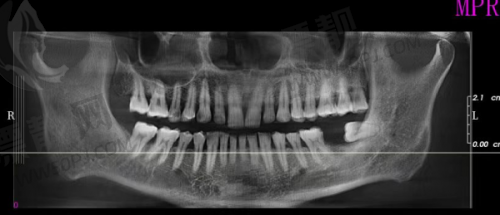

医院成立时间虽不算久(2023年),但规模和配置那是步步到位——营业面积4000㎡,共开设12个科室,一医一患一诊室,完全隐私化。再配上蔡司显微镜、数字化口腔CT、3D打印系统,做种植牙的连误差都可以严谨到0.1mm,这精度,堪比你媳妇打你脸时的准度。